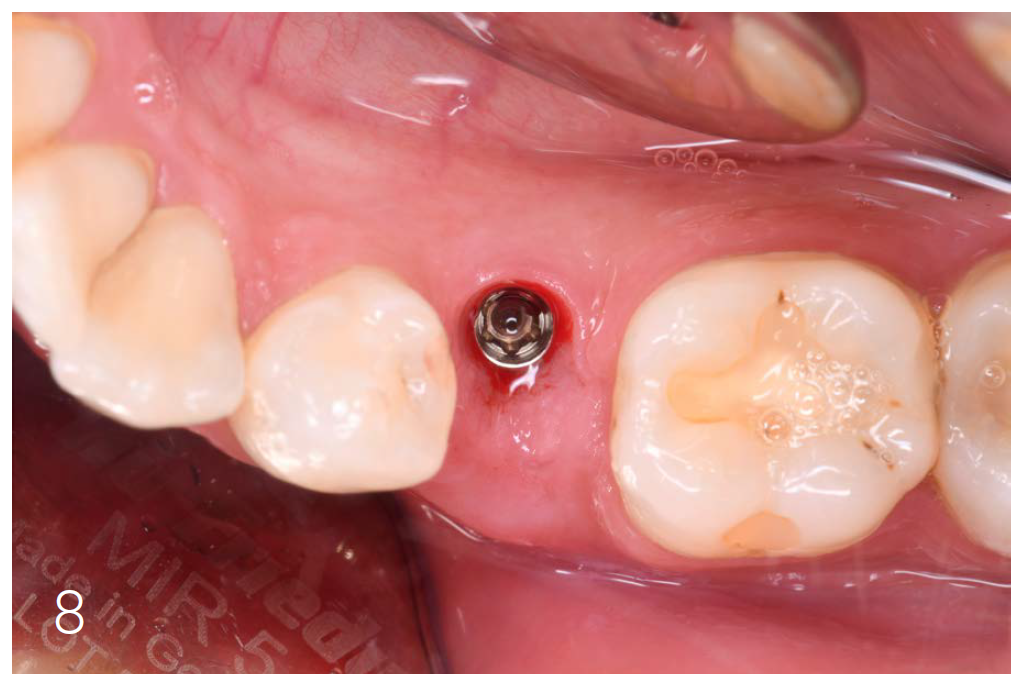

Figure 4: Condition after implantation

After osteotomy, I placed a 3.75 mm diameter implant, filled the gap between implant and root surface with allogenic bone substitute, inserted a provisional, and later restored with an aesthetic ceramic crown.

Figures 7 and 8: Clinical situation after 6 months